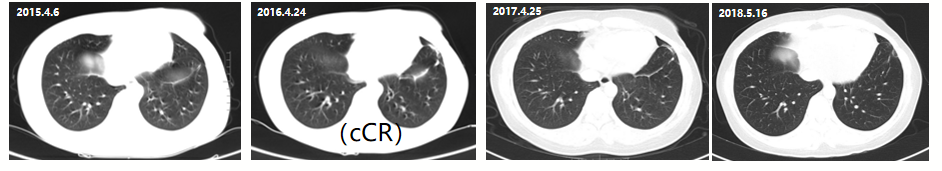

2015年4月至2018年5月,患者使用拉帕替尼+卡培他滨作为二线治疗方案,最佳疗效评估为临床完全缓解(CR),无进展生存期为38+个月,2018年5月停药。

图1 患者在2015年4月至2018年5月期间肺转移灶影像结果